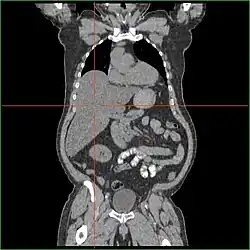

Hepatomegaly via CT scan.

Hepatomegaly with enlarged liver visible in red crosshairs and extending downward.

Impairment in the liver's ability to perform gluconeogenesis leads to clinically apparent hepatomegaly. Without this process, the body is unable to liberate glycogen from the liver and convert it into blood glucose, leading to an accumulation of stored glycogen in the liver. Hepatomegaly from the accumulation of stored glycogen in the liver is considered a form of non-alcoholic fatty liver disease. GSD I patients present with a degree of hepatomegaly throughout life, but severity often relates to the consumption of excess dietary carbohydrate. Reductions in the mass of the liver are possible since most patients retain residual hepatic function that allows for the liberation of stored glycogen at a limited rate.

GSD I patients often present with hepatomegaly from the time of birth. In fetal development, maternal glucose transferred to the fetus prevents hypoglycemia, but the storage of glucose as glycogen in the liver leads to hepatomegaly. There is no evidence that this hepatomegaly presents any risk to proper fetal development.

Hepatomegaly in GSD type I generally occurs without sympathetic enlargement of the spleen. GSD Ib patients may present with splenomegaly, but this is connected to the use of filgrastim to treat neutropenia in this subtype, not comorbid hepatomegaly. Hepatomegaly will persist to some degree throughout life, often causing the abdomen to protrude, and in severe cases may be palpable at or below the navel. In GSD-related non-alcoholic fatty liver disease, hepatic function is usually spared, with liver enzymes and bilirubin remaining within the normal range. However, liver function may be affected by other hepatic complications in adulthood, including the development of hepatic adenomas.